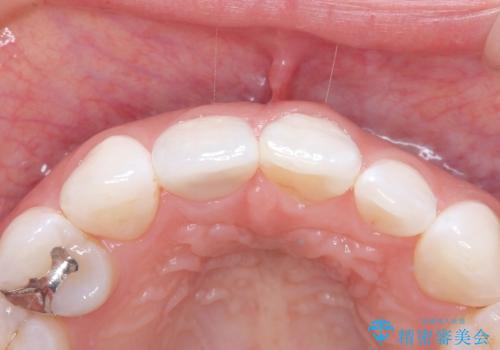

- 患者様は、前歯の被せ物の形や色が不自然で気になるというお悩みを抱えて来院されました。

診察の結果、既存の被せ物は古い素材で作られており、周囲の歯との調和が難しいことが分かりました。患者様とカウンセリングを重ね、アライナー矯正で歯列のガタツキを修正後、。より自然で審美的な仕上がりを目指してオールセラミッククラウンでの治療を提案しました。

オールセラミッククラウンは、金属を使用しないため、自然光の下でも透過性が高く、天然歯と見分けがつかないほど美しい仕上がりが得られる素材です。また、金属アレルギーの心配がなく、長期間使用しても歯ぐきへの影響が少ないという利点があります。